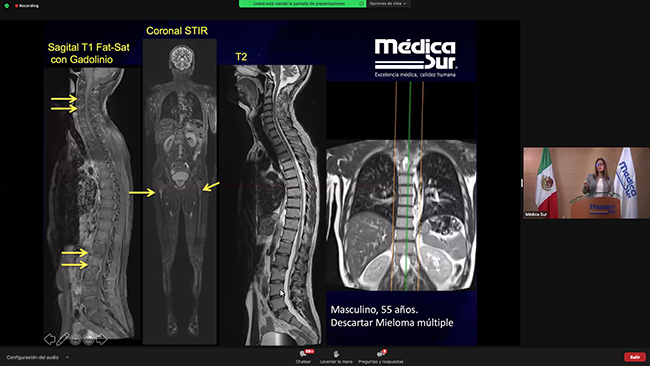

Por primera vez se llevó a cabo el 3 y 4 de febrero de 2022 el Congreso de Resonancia Magnética, organizado por el departamento de Resonancia Magnética de Médica Sur en formato virtual.

Se presentaron 26 conferencias y 2 talleres de casos clínicos, todos impartidos por médicos, residentes y adscritos de Médica Sur y de otras instituciones. Los temas principales que se abordaron fueron los usos de la Resonancia Magnética en: Corazón, Mama, Neurología, Sistema músculo esquelético, Patología oncológica y Abdomen / pelvis.

13:30 - 14:00 · Aplicaciones y uso del contraste hepato-específico

Dr. Raúl Batista Quiroz

16:10 - 17:00 · Taller de casos clínicos